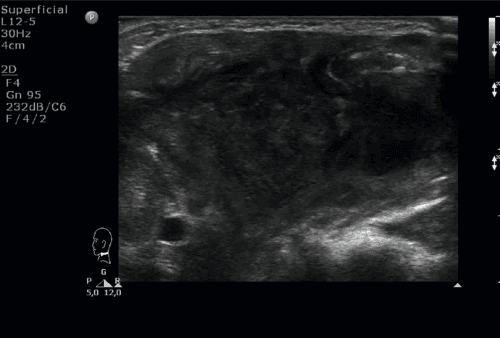

Chłopiec niespełna 16-letni zgłosił się do izby przyjęć z powodu bólu i obrzęku szyi po stronie lewej. Dwa tygodnie wcześniej dziecko przebyło infekcję dróg oddechowych z kaszlem, bez gorączki. Dodatkowo od około tygodnia chłopiec skarżył się na poty nocne. Przy przyjęciu stan ogólny dziecka był dobry, w badaniu fizykalnym z odchyleń od normy: obrzęk szyi, bolesność uciskowa po stronie lewej; ruchomość szyi zachowana. Stwierdzono liczne, drobne węzły chłonne szyjne oraz obecne znacznie powiększone węzły limfatyczne nadobojczykowe i podobojczykowe po stronie prawej. W badaniach laboratoryjnych podwyższona wartość OB. W rtg klatki piersiowej uwidoczniono poszerzenie cienia śródpiersia przedniego. W wykonanym badaniu USG na szyi głównie po stronie prawej i nadobojczykowo zobrazowano liczne węzły chłonne o znacznie zmienionej morfologii, hipoechogeniczne lub o mieszanej echogeniczności, ze słabo widoczną wnęką i wzmożonym unaczynieniem. W pomiarach: węzły nadobojczykowe po stronie prawej wielkości 32 x 9 mm, kolejny 22 x 14 mm (z możliwymi cechami rozpadu), kilka węzłów do 13 mm widocznych było częściowo zamostkowo (najprawdopodobniej w śródpiersiu); po stronie lewej nadobojczykowo obecne były liczne, drobne, hipoechogeniczne węzły chłonne. Unaczynienie węzłów limfatycznych było chaotyczne, zobrazowano naczynia wnikające z obwodu. Dodatkowo uwidoczniono zakrzepicę żyły szyjnej wewnętrznej prawej. Zdecydowano o chirurgicznym usunięciu jednego z węzłów chłonnych. Istotny jest fakt, że do badań histopatologicznych u dzieci pobiera się cały węzeł chłonny. Nie wykonuje się biopsji cienkoigłowej z uwagi na znaczny odsetek niediagnostycznych wyników. Na podstawie badania hist-pat rozpoznano chłoniaka Hodgina i rozpoczęto leczenie onkologiczne.